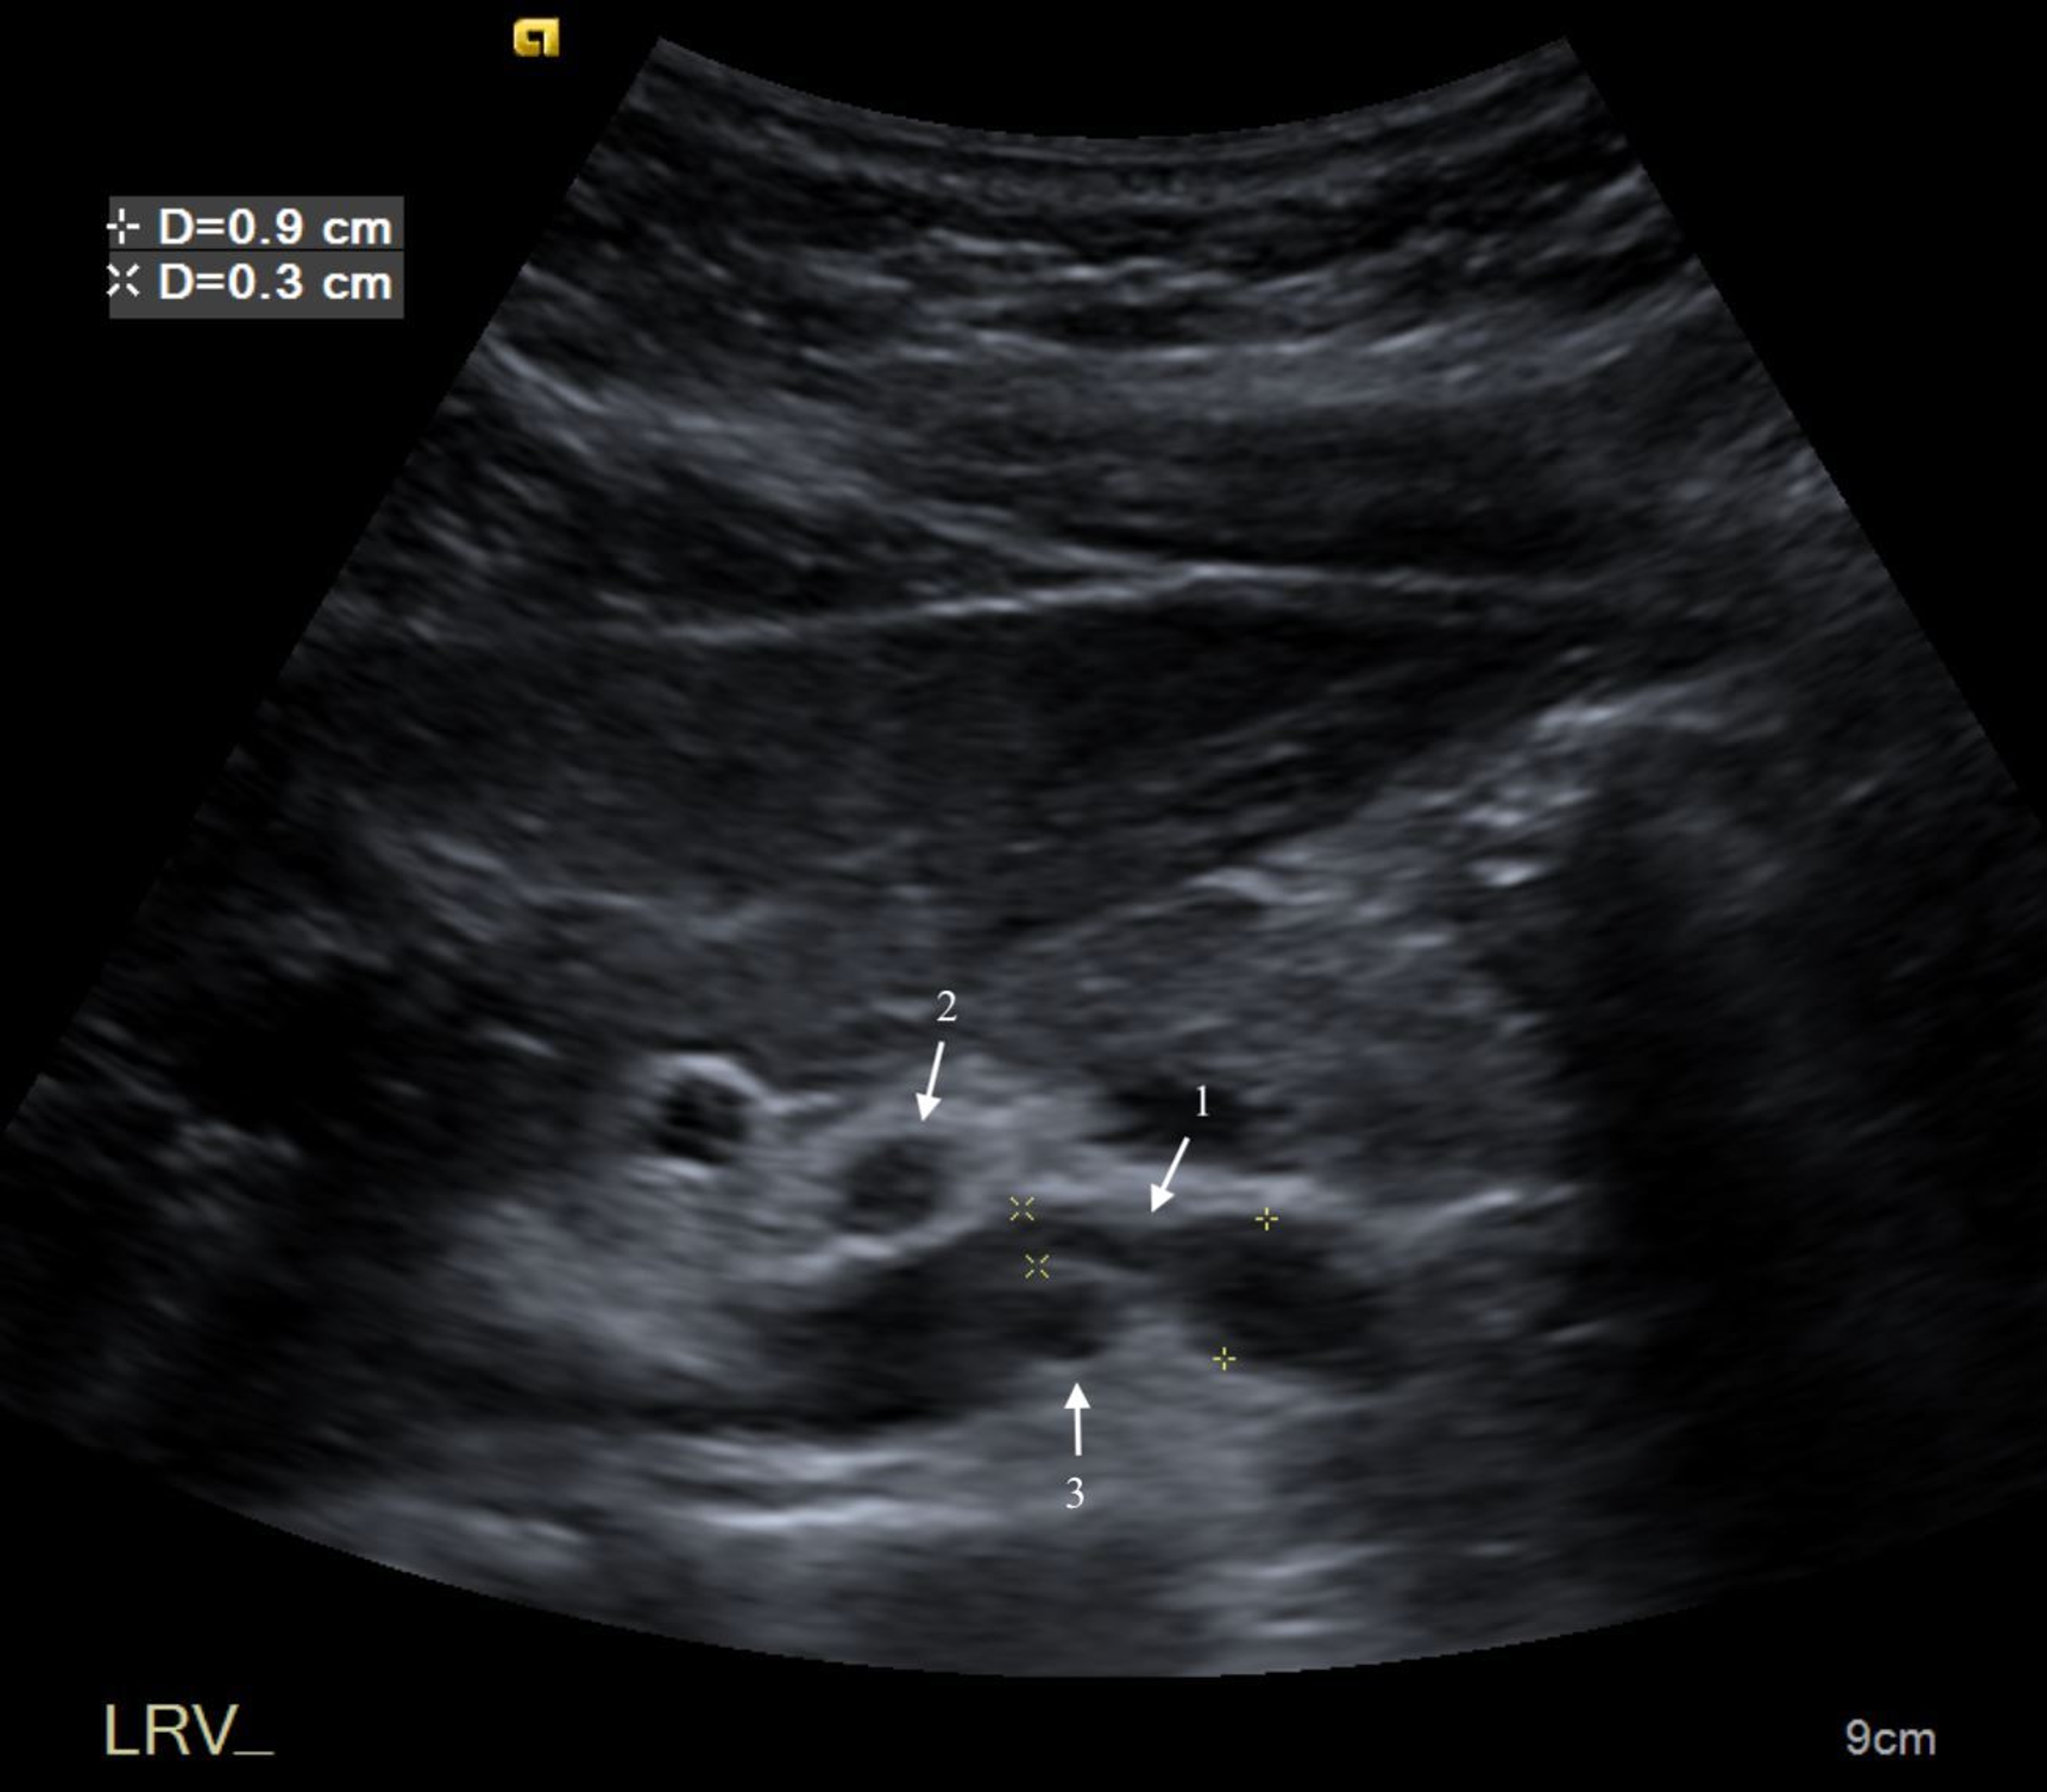

From www.reddit.com

Nutcracker syndrome on ultrasound. r/Radiology Nutcracker Syndrome Pain On Right Side the clinical term of nutcracker syndrome corresponds to the additional presence of symptoms. The condition has this name because the. Diagnosis is usually made after. Macro and micro hematuria, proteinuria, and flank pain. anatomic compression of the left renal vein in the angle between the aorta and superior mesenteric artery may be asymptomatic or may. left renal. Nutcracker Syndrome Pain On Right Side.